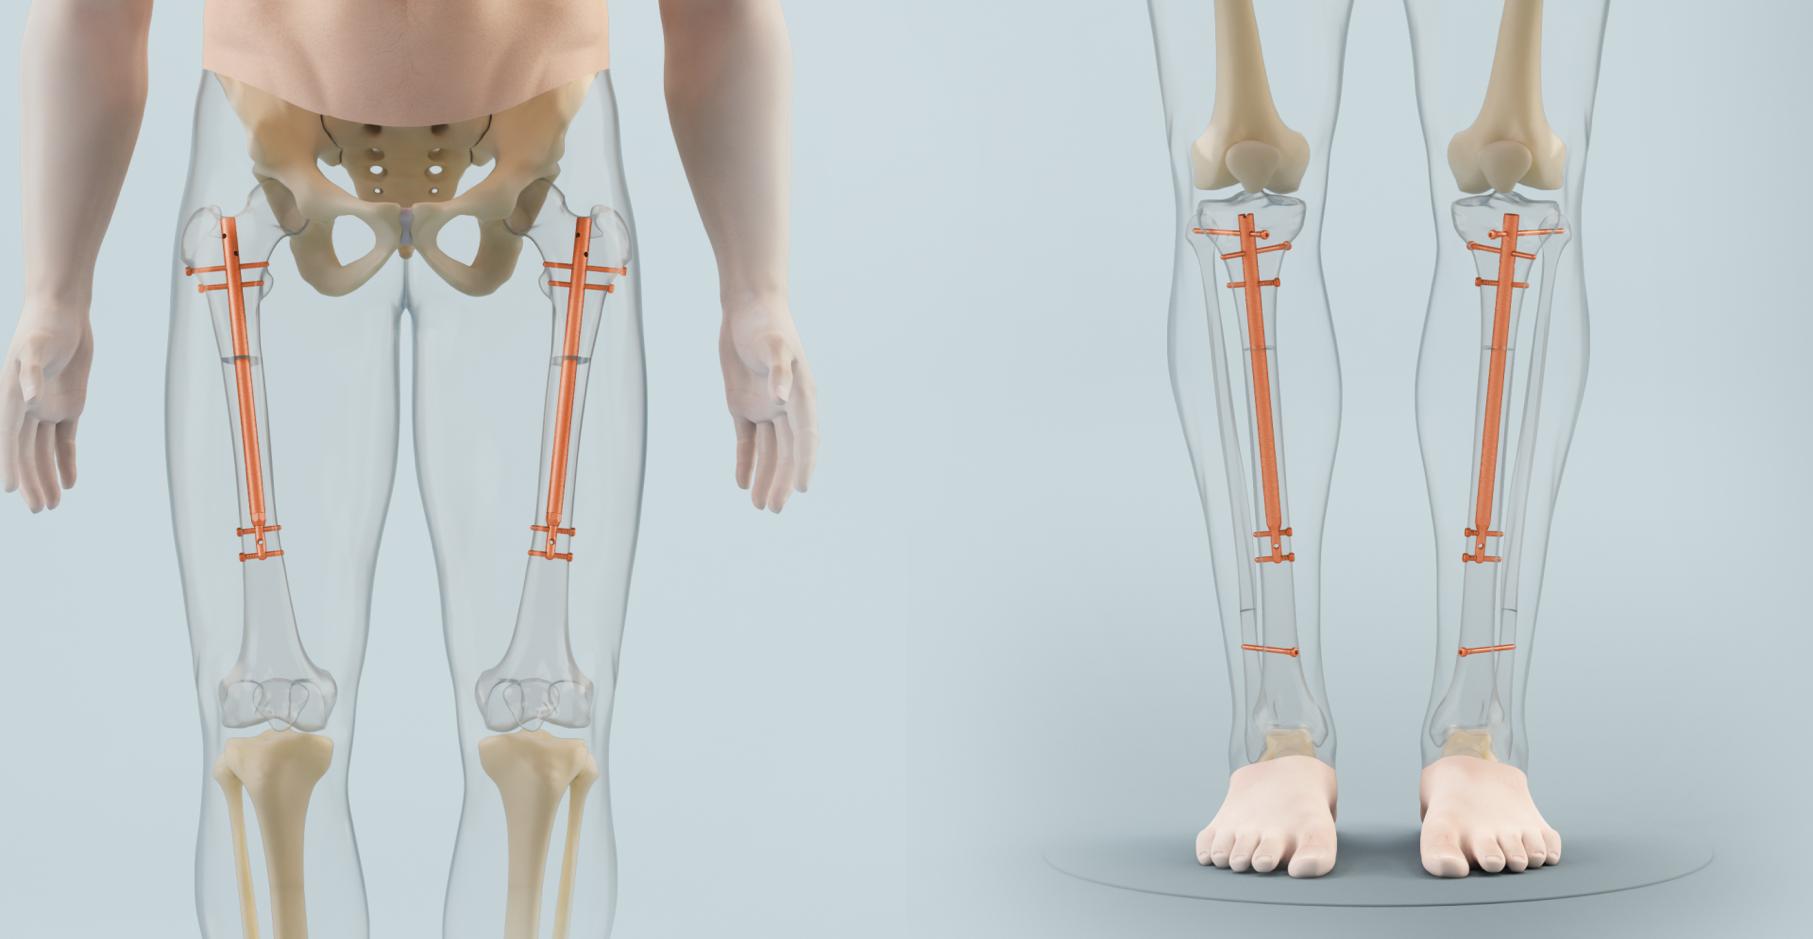

Voll implantierbare Distraktionsmarknägel:

Um die Möglichkeiten der Kallusdistraktion zu nutzen, ohne die Nachteile der externen Fixateure in Kauf nehmen zu müssen, wurden seit den 1980er Jahren voll implantierbare Distraktionsmarknägel entwickelt. Konventionelle Marknägel aus Stahl oder Titan werden

schon seit über 50 Jahren in der Behandlung von Knochenbrüchen verwendet. Auf solchen Marknägeln basieren alle heute auf dem Weltmarkt erhältlichen Distraktionsmarknägel. Diese besitzen ein ausgeklügeltes Innenleben, das ihnen die Distraktion erlaubt.

Der Fitbone II® wurde von Prof. Dr. med. Betz entwickelt. Er ist eine Weiterentwicklung des von Prof. Dr. med. Betz und Prof. Dr. med. Baumgart entwickelten Fitbone I®. Fitbone I® wird jedoch nur noch selten verwendet. Die Verlängerung des Nagels erfolgt durch einen Elektromotor im Nagelinneren, der von außen mit Energie (Auflage eines Senders durch die Haut) versorgt wird. Fitbone II® erscheint leicht bedienbar ohne aktive Mitarbeit des Patienten und ist bis heute der einzige Nagel für simultane Vierfachverlängerungen. Der Nagel ist teuer, die Stabilität und Kontrollierbarkeit sind limitiert, häufige klinische, sonographische und Röntgenkontrollen sind erforderlich. Er erlaubt die kürzeste maximale Distraktion aller verfügbarer Distraktionsmarknägel.

Der Albizzia® ist ein von Drs. Guichet und Grammont entwickelter mechanischer Distraktionsnagel, bei dem die Verlängerung durch drehende Hin- und Herbewegungen des betroffenen Beines um 20o bis zu einem hörbaren Klickton erfolgt. Der von Prof. Dr. med. Betz verwendete BetzboneÒ ist eine Weiterentwicklung bzw. Modifikation und Verbesserung des Albizzia®. Das Material des Nagels hat eine höhere Festigkeit und die Verriegelung im Knochen wurde besser an die Anatomie des Knochens angepasst. Der BetzboneÒhat die höchste Stabilität und Verlängerungskapazität mit bis zu 12 cm aller zurzeit am Markt befindlichen intramedullären Distraktionsmarknägel. Die hohe Stabilität erlaubt eine frühe Vollbelastung und uneingeschränkte Physiotherapie direkt nach der Operation, einen zuverlässigen Vorschub mit sicherer Funktion und erfordert nur wenige klinische und Röntgenkontrollen. Die erstmalige Aktivierung des Verlängerungsmechanismus erfordert eine sensible Anleitung durch den Operateur. Er hat ein gutes Preis-Leistungsverhältnis.

BetzboneÒ

Fitbone II® im Unterschenkel Albizzia® im Oberschenkel BetzboneÒ im Oberschenkel